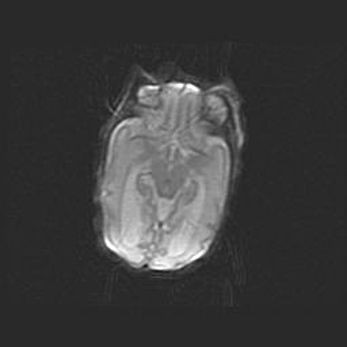

Лейкомаляция с кистозно-глиозной дегенерацией головного мозга.

Возраст: 2 месяца 25 дней

Вес: 6400 г

Окружность головы: 40 см

Срок гестации: 41 неделя

Лейкомаляцию относят к ишемически-гипоксическим повреждениям головного мозга, диагностируемым у новорожденных. При лейкомаляции в головном мозге обнаруживают очаги некроза, возникшие после тяжелой гипоксии и нарушения кровотока. В процессе морфогенеза очаги проходят три стадии: 1) развития некроза, 2) резорбции и 3) формирования глиозного рубца или кисты. Перивентрикулярная лейкомаляция (ПЛ) встречается примерно в 12% случаев среди новорожденных, обычно – у недоношенных детей, причем, частота ее зависит от массы, с которой младенец появился на свет. Наибольшее число малышей страдает лейкомаляцией, если масса при рождении 1500-2500 г.